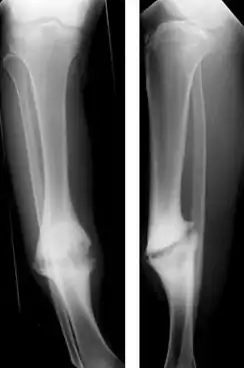

| Hypertrophic nonunion of the tibia | |

Hypertrophic non-union

Callus is formed, but the bone fractures have not joined. This can be due to inadequate fixation of the fracture, and treated with rigid immobilisation.

Atrophic non-union

No callus is formed. This is often due to impaired bony healing, for example due to vascular causes (e.g. impaired blood supply to the bone fragments) or metabolic causes (e.g. diabetes or smoking). Failure of initial union, for example when bone fragments are separated by soft tissue may also lead to atrophic non-union. Atrophic non-union can be treated by improving fixation, removing the end layer of bone to provide raw ends for healing, and the use of bone grafts.